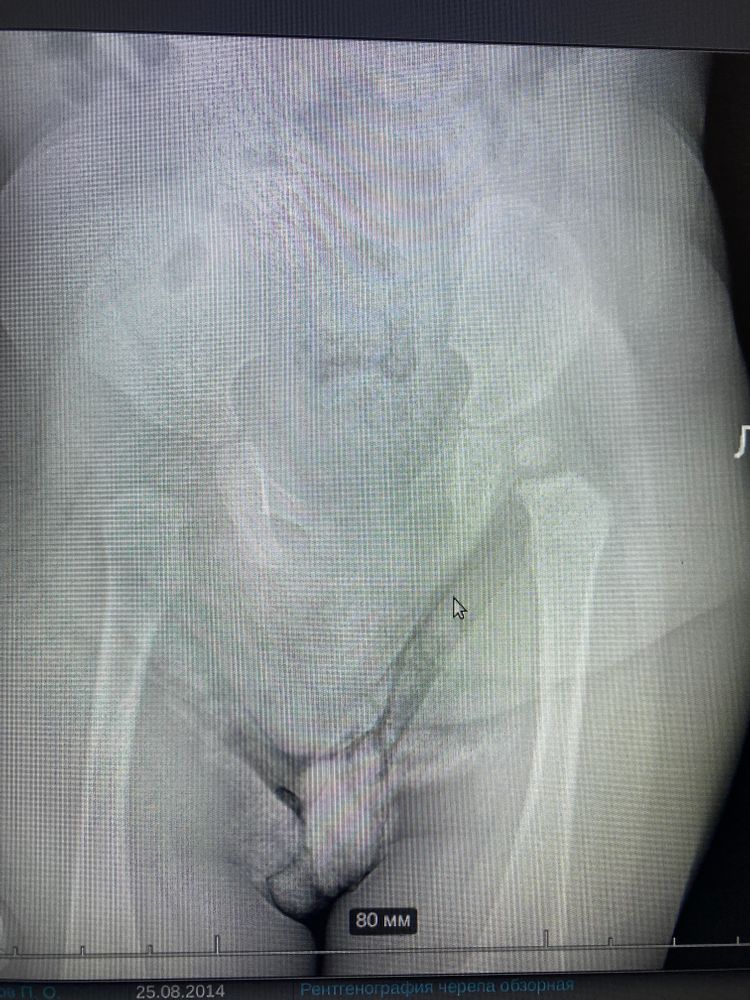

А врач что сказал? Они же там углы меряют, смотрят, окостенение. Ну визуально слева не так чётко.